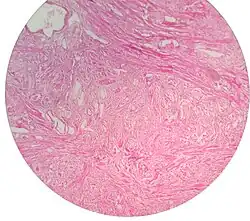

Micrograph showing nodular hyperplasia (left off center) of the prostate from a transurethral resection of the prostate (TURP). H&E stain.

Micrograph showing nodular hyperplasia (left off center) of the prostate from a transurethral resection of the prostate (TURP). H&E stain. -